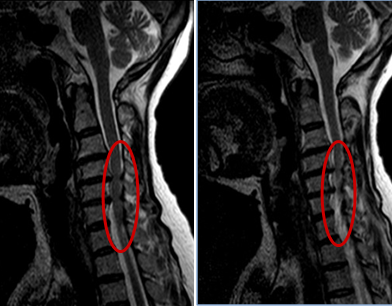

入院后完善各项辅助检查,赖奶奶的颈椎DR显示: 颈椎生理曲度变直;各颈椎椎体骨质完整,C3-6椎体边缘见骨质增生,C3/4、4/5、5/6椎间隙稍变窄,双侧C3/4、4/5、5/6椎间孔变窄;齿状突居中。颈椎MR示:1.颈椎退行性变,椎体欠稳;2.颈3/4、颈4/5、颈5/6椎间盘向后突出;颈4/5水平椎管狭窄,局部颈髓受压变性。

术前MR